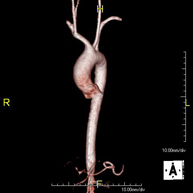

Prova diagnòstica no invasiva que consisteix en l'estudi de l'artèria aorta abdominal i de les artèries ilíaques, amb l'obtenció d'imatges d'alta definició anatòmica mitjançant l'ús d'un camp electromagnètic i ones de ràdio (amb un emissor i un receptor). És indispensable l'ús de contrast paramagnètic (Gadolini). No utilitza radiació ionitzant. La qualitat de les imatges permet realitzar reconstruccions en 2D i 3D. Aquesta prova està especialment indicada com a estudi prequirúrgic (mapa vascular) abans d'intervencions percutànies o quirúrgiques d'aorta abdominal i artèries ilíaques, per a l'estudi complementari en pacients amb isquèmia de membres inferiors, etc. - Angio RM Arterial d'extremitats inferiors

Prova diagnòstica no invasiva que consisteix en l'estudi de l'artèria aorta abdominal per obtenir imatges d'alta definició anatòmica mitjançant l'ús d'un camp electromagnètic i ones de ràdio (amb un emissor i un receptor). És indispensable l'ús de contrast intravenós paramagnètic (Gadolini). No obstant, no utilitza radiació ionitzant. La qualitat de les imatges permet realitzar reconstruccions en 2D i 3D. Està indicat en aquells pacients amb malaltia vascular (Aterosclerosi), per a l'estudi d'aneurismes, en estudis prequirúrgics de lesions adjacents a l'aorta abdominal com "mapa" vascular, etc. - Angio-RM Aorta ilíaca

Prova diagnòstica no invasiva que consisteix en l'estudi de l'artèria aorta abdominal per obtenir imatges d'alta definició anatòmica mitjançant l'ús d'un camp electromagnètic i ones de ràdio (amb un emissor i un receptor). És indispensable l'ús de contrast intravenós paramagnètic (Gadolini). No obstant, no utilitza radiació ionitzant. La qualitat de les imatges permet realitzar reconstruccions en 2D i 3D. Aquesta prova està especialment indicada com estudi prequirúrgic (mapa vascular) abans d'intervencions percutànies o quirúrgiques d'aorta abdominal, per a l'estudi complementari en pacients amb isquèmia de membres inferiors, etc. - Angio-RM d'Artèries renals